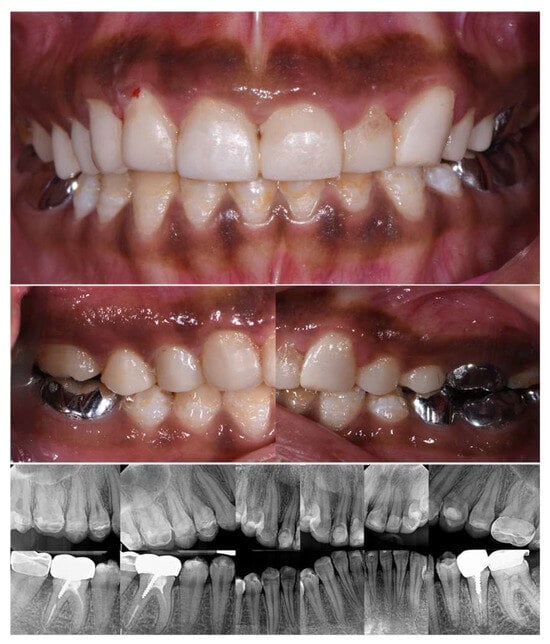

2.2. Clinical Examination

2.3. Radiographic Examinations